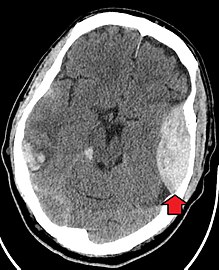

The primary clinical concern with blunt trauma to the head is damage to the brain, although other structures, including the skull, face, orbits, and neck are also at risk.[9] Following assessment of the patient's airway, circulation, and breathing, a cervical collar may be placed if there is suspicion of trauma to the neck. Evaluation of blunt trauma to the head continues with the secondary survey for evidence of cranial trauma, including bruises, contusions, lacerations, and abrasions. In addition to noting external injury, a comprehensive neurologic exam is typically performed to assess for damage to the brain. Depending on the mechanism of injury and examination, a CT scan of the skull and brain may be ordered. This is typically done to assess for blood within the skull, or fracture of the skull bones.[18]

Traumatic brain injury (TBI) is a significant cause of morbidity and mortality and is most commonly caused by falls, motor vehicle accidents, sports- and work-related injuries, and assaults. It is the most common cause of death in patients under the age of 25. TBI is graded from mild to severe, with greater severity correlating with increased morbidity and mortality.[18][19]

Most patients with more severe traumatic brain injury have of a combination of intracranial injuries, which can include diffuse axonal injury, cerebral contusions, and intracranial bleeding, including subarachnoid hemorrhage, subdural hematoma, epidural hematoma, and intraparenchymal hemorrhage.[9][18] The recovery of brain function following a traumatic accident is highly variable and depends upon the specific intracranial injuries that occur, however there is significant correlation between the severity of the initial insult as well as the level of neurologic function during the initial assessment and the level of lasting neurologic deficits.[18] Initial treatment may be targeted at reducing the intracranial pressure if there is concern for swelling or bleeding within this skull, which may require surgery such as a hemicraniectomy, in which part of the skull is removed.[9][18]